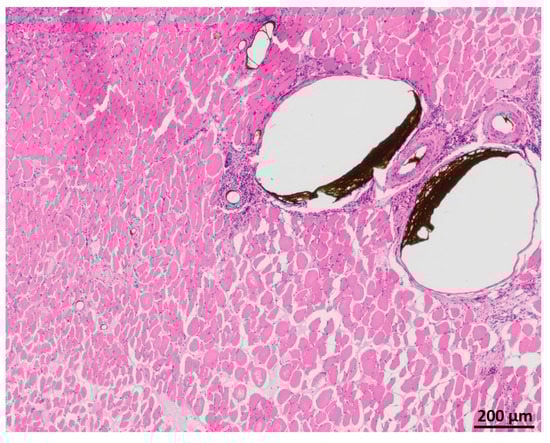

3.5. Myofiber Morphology and Macrophage Invasion

HE staining showed partly well-preserved structures as well as partly inhomogenous and irregularly arrangement of the skeletal muscle similar to MHC staining (Figure 11). CD68 staining revealed invasion of macrophages, especially near the vessels (Figure 12).

Figure 11. HE staining of the transplanted muscle showing partly well-preserved structures as well as partly inhomogenous and irregularly arrangement of the skeletal muscle.

Figure 12. CD68 staining of transplanted muscle showing macrophages predominantly near the vessels filled with Microfil®.